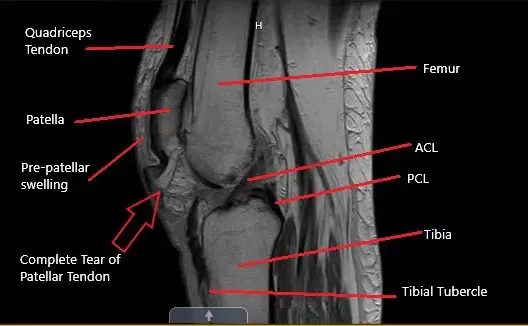

Resonancia magnética de la rodilla en la sección sagital que muestra una rotura completa del tendón rotuliano

La resonancia magnética de la rodilla izquierda sugirió una rotura de sustancia media de grosor completo del tendón rotuliano con un espacio de líquido de aproximadamente 1,7 cm y la rótula alta asociada. Hubo infiltración/edema difuso en la grasa infrapatela y prepatelar. El paciente es un banquero jubilado y llevaba un estilo de vida activo antes de la lesión.